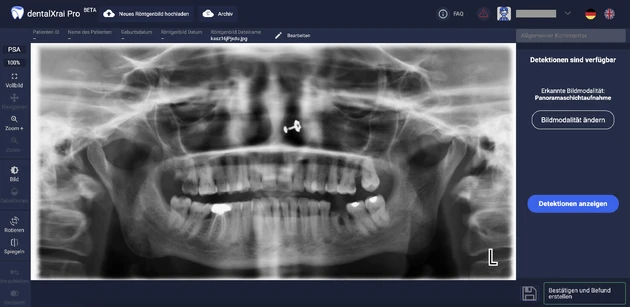

Antwort: Ein wichtiges Anwendungsgebiet ist die Röntgenbildanalyse, zum Beispiel bei der Befundung von Einzelbildern, Bissflügelaufnahmen, Panoramaschichtaufnahmen und Fernröntgenseitenbildern. Weltweit arbeiten einige Forschergruppen daran, KI-Modelle zu entwickeln, die einerseits physiologische Strukturen wie Zähne und Knochen, aber auch zahnärztliche Restaurationen wie Kronen, Implantate oder Füllungen erkennen können. Zudem können auch pathologische Zustände wie Karies, Knochenabbau oder apikale Läsionen erkannt werden.

Antwort: Ich sehe eine Entlastung des Zahnmediziners als ein Vorteil. Die KI-Software erstellt einen systematischen Vorbefund, den der Zahnarzt nur noch einmal kontrollieren muss. Manche Läsionen erkennt eine KI-Anwendung sogar zuverlässiger als ein Zahnarzt, wie die eben erwähnten frühen Stadien einer Approximalkaries. Die farbige Kenntlichmachung dieser Läsionen auf dem Röntgenbild erlaubt zudem eine einfachere Kommunikation mit dem Patienten.

Antwort: Für die Patientenkommunikation und die Diagnose-Unterstützung macht eine Anschaffung heute schon Sinn. Eine Software braucht beispielsweise nur zehn Sekunden, um eine Panoramaschichtaufnahme zu befunden. Der Zahnarzt kontrolliert das und speichert den Befund. Das dauert insgesamt etwa eine Minute. Allein aus Schnelligkeitsgründen sind solche Systeme heute schon nützlich – und sie werden ja stetig besser! Diese Anwendungen sind nicht nur für Spezialisten und Großpraxen nützlich, sondern im Prinzip für die ganze Breite der Zahnarztpraxen, denn jedes datengenerierende Gerät in einer Praxis ist potenziell geeignet, mit KI zusammenzuarbeiten.